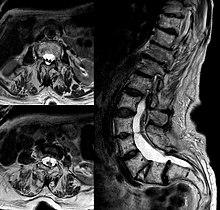

Diastematomelia in MRI of lumbar spine.

Adult presentation in diastematomyelia is unusual. With modern imaging techniques, various types of spinal dysraphism are being diagnosed in adults with increasing frequency. The commonest location of the lesion is at first to third lumbar vertebrae. Lumbosacral adult diastematomyelia is even rarer. Bony malformations and dysplasias are generally recognized on plain x-rays. MRI scanning is often the first choice of screening and diagnosis. MRI generally give adequate analysis of the spinal cord deformities although it has some limitations in giving detailed bone anatomy. Combined myelographic and post-myelographic CT scan is the most effective diagnostic tool in demonstrating the detailed bone, intradural and extradural pathological anatomy of the affected and adjacent spinal canal levels and of the bony spur.